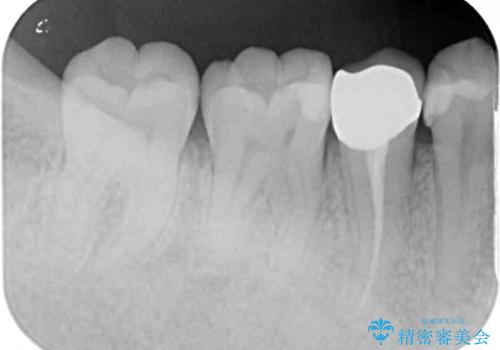

- 神経を抜く処置の後に装着したプラスチックのクラウンが外れてしまったとのことで来院された患者様です。

患者様自身、神経の取り除かれた歯はしっかりと製作されたクラウンを装着するべきと理解していただいていたため、オールセラミッククラウンにて補綴治療することとしました。

丈夫なクラウンを装着できただけでなく、形態や色調も自然に仕上げることができました。